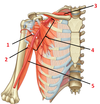

Subscapularis

1? 2?

1: Infraspitanus muscle

2: Teres minor muscle

1?

1: Supraspinatus muscle

1?

1: Deltoid muscle

1?

Pectoralis major muscle

1?

1: Pectoralis minor muscle

1?

1: Serratus anterior muscle